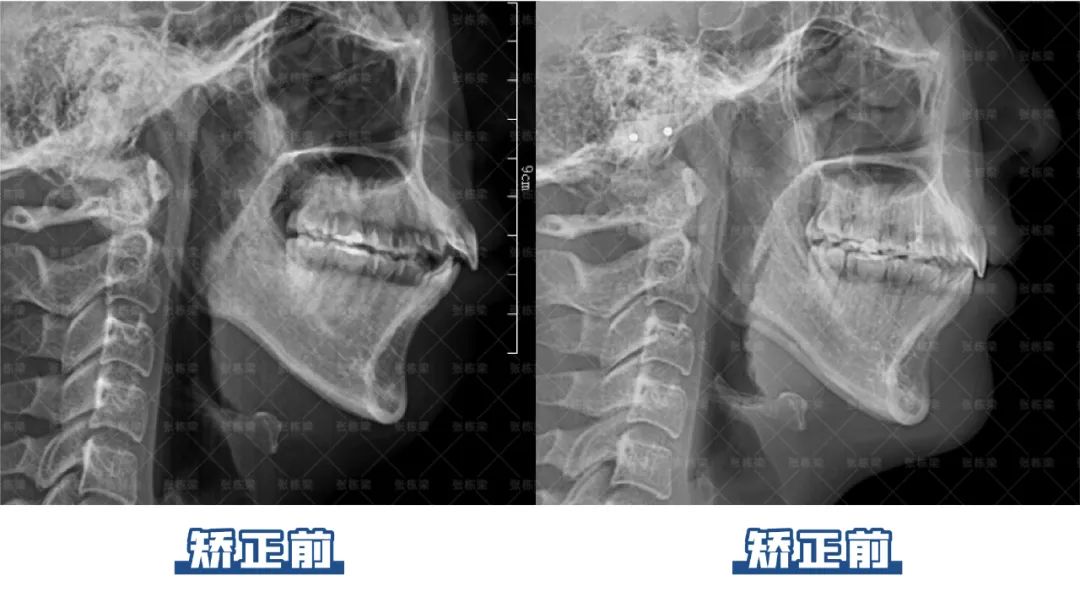

这个女孩主诉牙不齐、下巴后缩、关节弹响问题,她的诉求是想要牙齿恢复整齐,改善没下巴的情况,减轻关节压力。

结合牙片资料和口内情况检查发现,她是高角面型,骨性II类,上颌前突,下颌后缩,前牙3-3 II度拥挤。综合分析牙片面型制定牙齿矫正目标